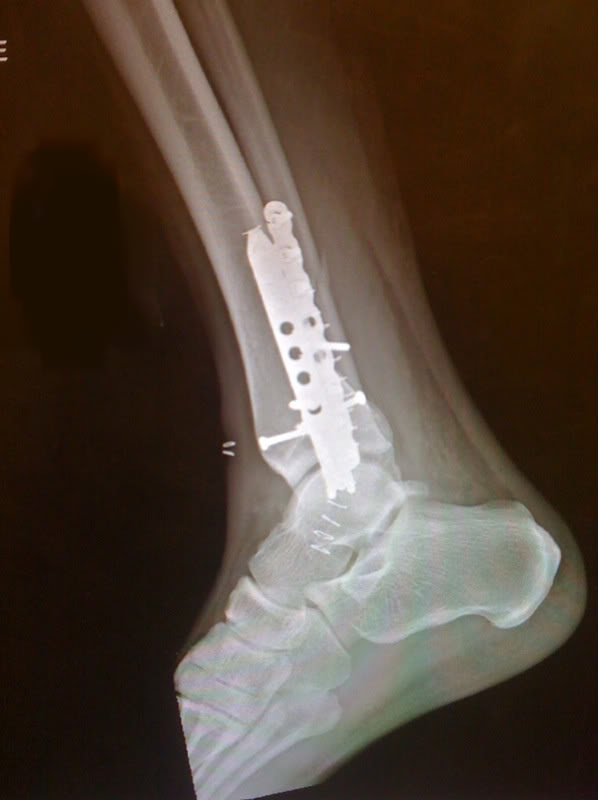

Nearly twisting my foot off the end of my leg, and now having an ankle that looks something like this is probably the reason. LOL! Let me put it this way. My knee was straight, and my foot was pointing left between a 45° and 90° angle. I’m not kidding (picture me with my tongue hanging out). They gave me laughing gas in the ambulance, but I never did laugh. LOL! So glad I can laugh now ’cause it was more painful than natural childbirth. The end result is I haven’t been downhill skiing in awhile. I stick to cross country skiing, which has enough challenges, but there are no thrills like downhill. It’s just sheer, cussed work.